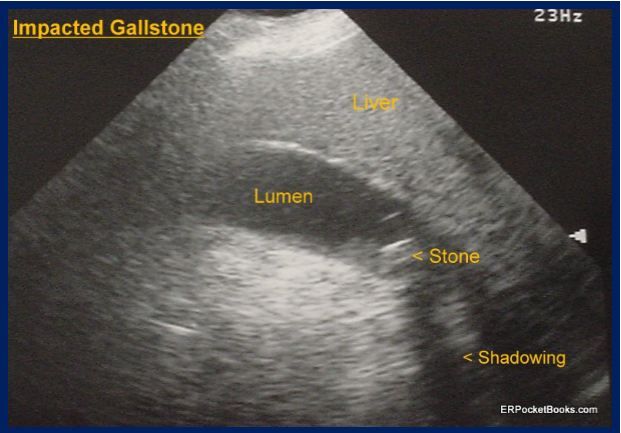

Figure 2. ED ultrasound, Dx, cholecystitis. Click to enlarge

Question 1. The ultrasound shows a gallstone impacted in the gallbladder neck (Figure 2). (Click image to enlarge).

When stones become impacted in the gallbladder neck they can cause cholecystitis. The hallmark of cholecystitis is pain lasting more than 6 hours, often associated with vomiting. In early or mild disease there may be no fever and blood tests are often all normal. In more severe cases LFT values and WBC count may elevate and fever may occur. Ultrasound, the initial imaging test of choice, may show a thickened gallbladder wall, a dilated common bile duct, or pericholecystic fluid, but in about 10% of cases, only gallstones will be noted. A nuclear biliary scan (HIDA or DESIDA) is about 95% sensitive and is considered the gold standard test. Treatment is surgical with adjuvant antibiotics.